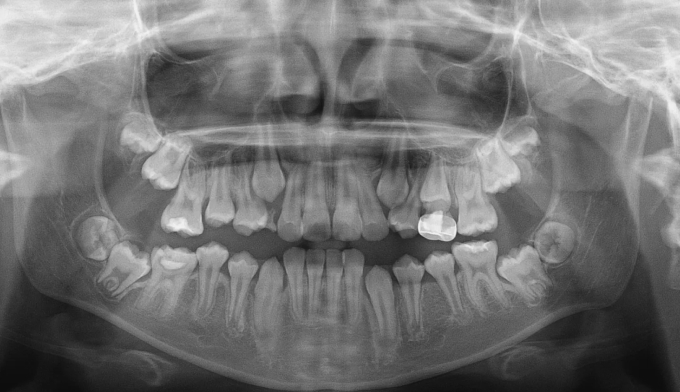

초등학교 4학년 남학생이 이가 고르지 못하고 송곳니가 나지 않는다고 합니다.

엑스레이를 찍어보니 치아가 나올 공간이 많이 부족하여 이가 고르지 못하고 송곳니가 나올 공간도 부족해 보였습니다. 정상적인 맹출 순서가 어긋나다보니 치열의 비대칭도 관찰됩니다.

약 8개월간의 공간확장치료를 통하여 이가 배열되고 송곳니가 나올 공간을 만들어주었습니다.

공간 확보 후 치아를 배열하여 교정 마무리 하였습니다.

총 교정기간은 22개월 소요되었습니다.